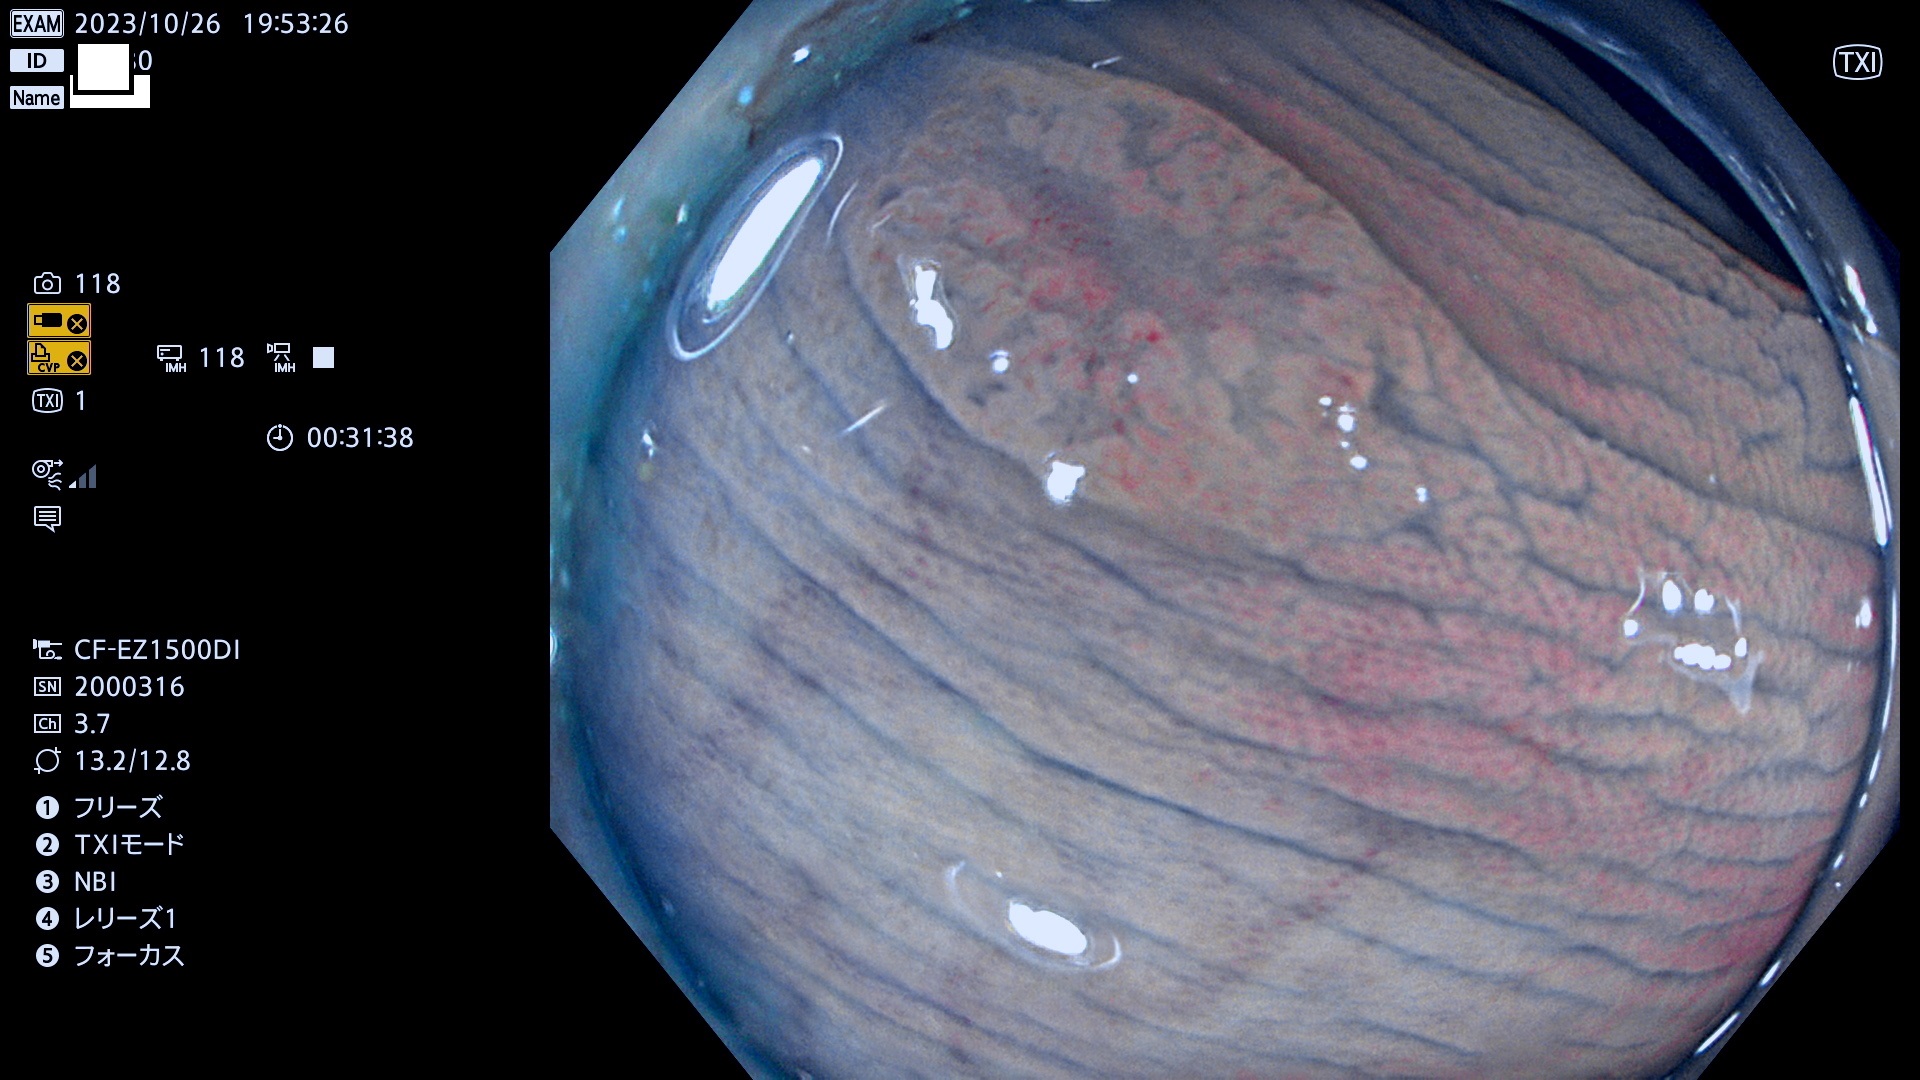

表面型腺腫(Flat Adenoma)の中で、完全に平坦な物をUb、陥凹している物をUcと呼びます。平坦隆起型(Ua)よりも、発見が難しく危険な病変です。このタイプは「内視鏡後・大腸癌の重要犯人」であり、この発見率は「腺腫発見率」よりも、重要な意味があります。

毎週の検査(木・金・土・日)に発見されたUb、Uc型・腺腫を、その週の日曜の夜にUPし1週間、提示します。

抽出の対象期間 2023年10月26日(木)〜10月30(月)の5日間(60件の検査)7件